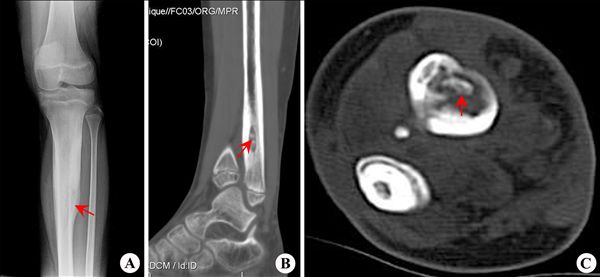

【影像表现】:X线正位(A)显示骨皮质增厚,髓腔变窄;CT矢状面MPR重建(B)显示增厚的骨皮质和髓腔内小块死骨;CT横断面(C)显示增厚的皮质和髓腔内死骨。

【影像诊断】:胫骨中上段慢性骨髓炎。